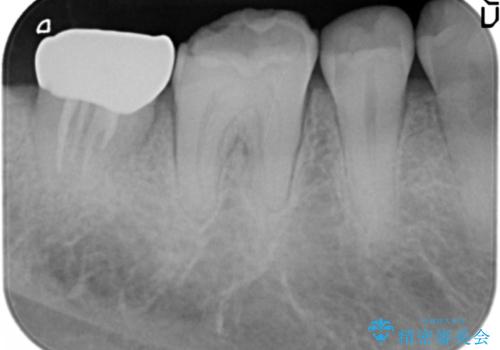

歯ぎしりによる異常に低い歯冠高径 歯周外科による解決

歯周外科を行い歯茎の位置を下げることで安定したクラウン製作ができる状態を目指します。

- 30万円(根管治療・歯周外科・ファイバーコア・ジルコニアクラウン)費用は治療当時の料金となります